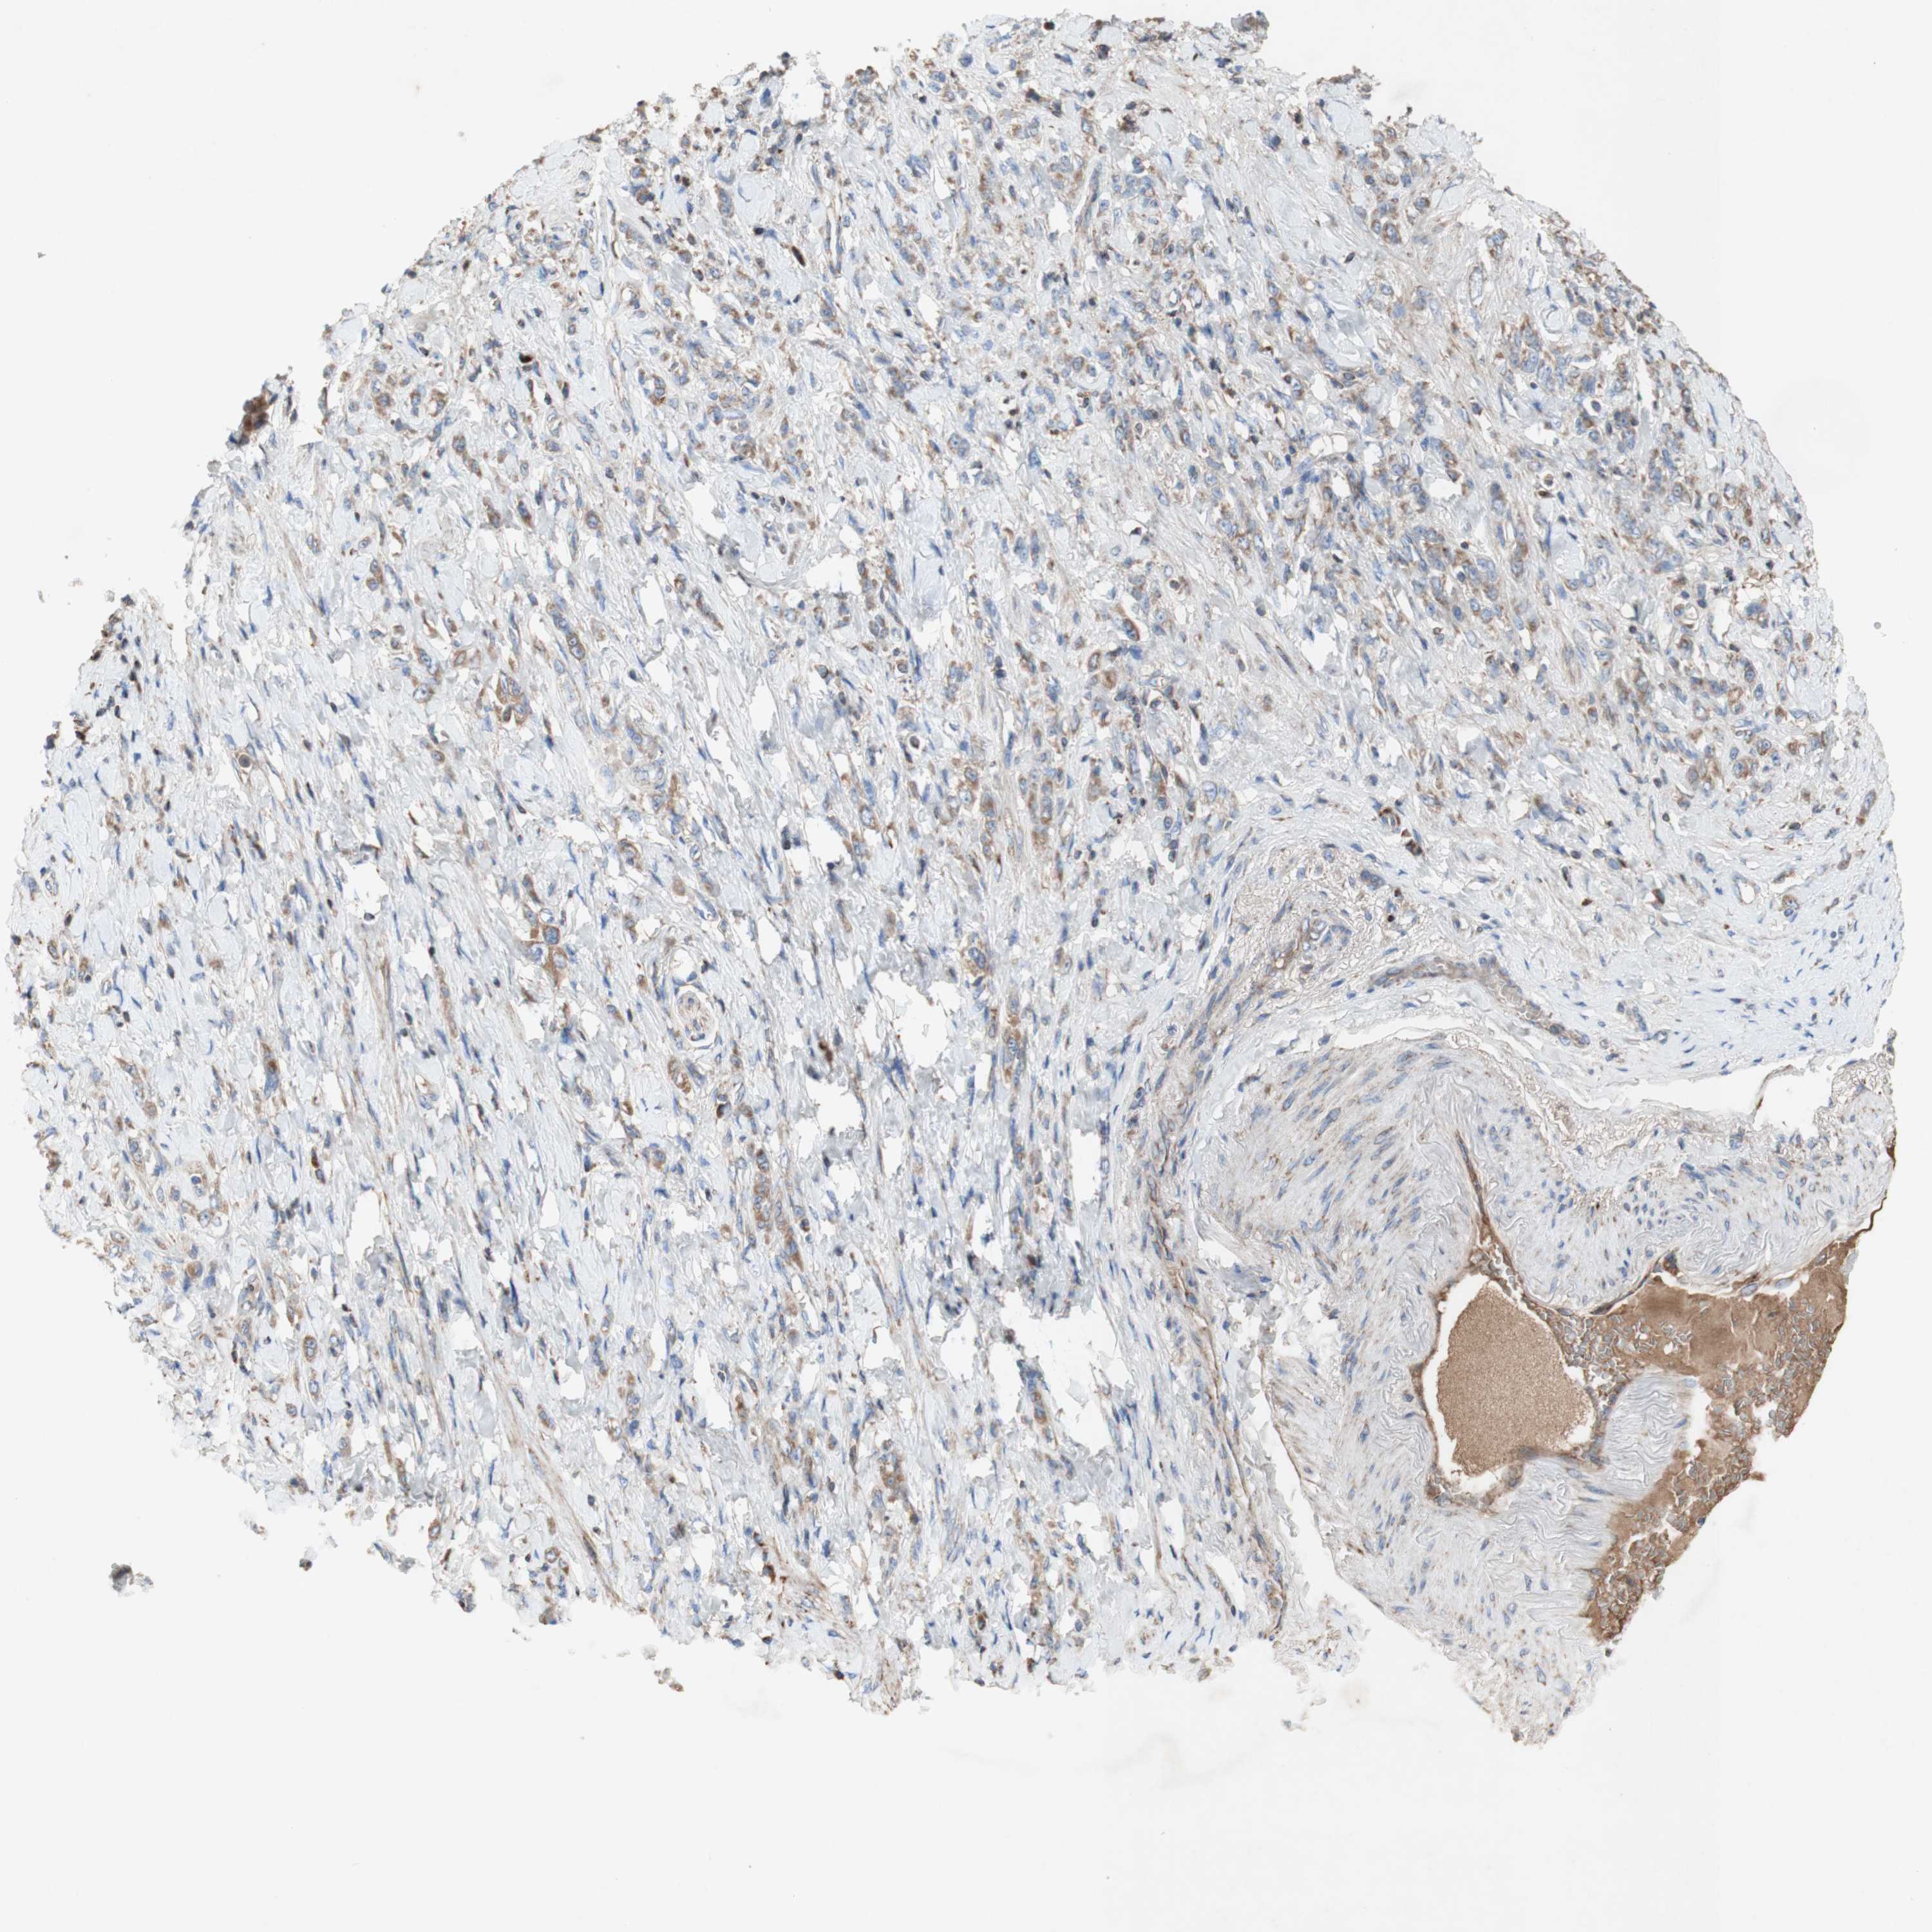

STOMACH CANCER - Protein expressioni

A mouse-over function shows sample information and annotation data. Click on an image to view it in a full screen mode. Samples can be filtered based on level of antibody staining by selecting one or several of the following categories: high, medium, low and not detected. The assay and annotation is described here.

Note that samples used for immunohistochemistry by the Human Protein Atlas do not correspond to samples in the TCGA dataset.

Antibody stainingi

Antibody staining in the annotated cell types in the current human tissue is reported as not detected, low, medium, or high, based on conventional immunohistochemistry profiling in selected tissues. This score is based on the combination of the staining intensity and fraction of stained cells.

Each image is clickable and will lead to virtual microscopy that enables deeper exploration of all samples and also displays staining intensity scores, fraction scores and subcellular localization as well as patient and tissue information for each sample.

HPA002868

CAB009822

CAB068233

CAB068234

CAB068235

Adenocarcinoma, NOS

Adenocarcinoma, High grade